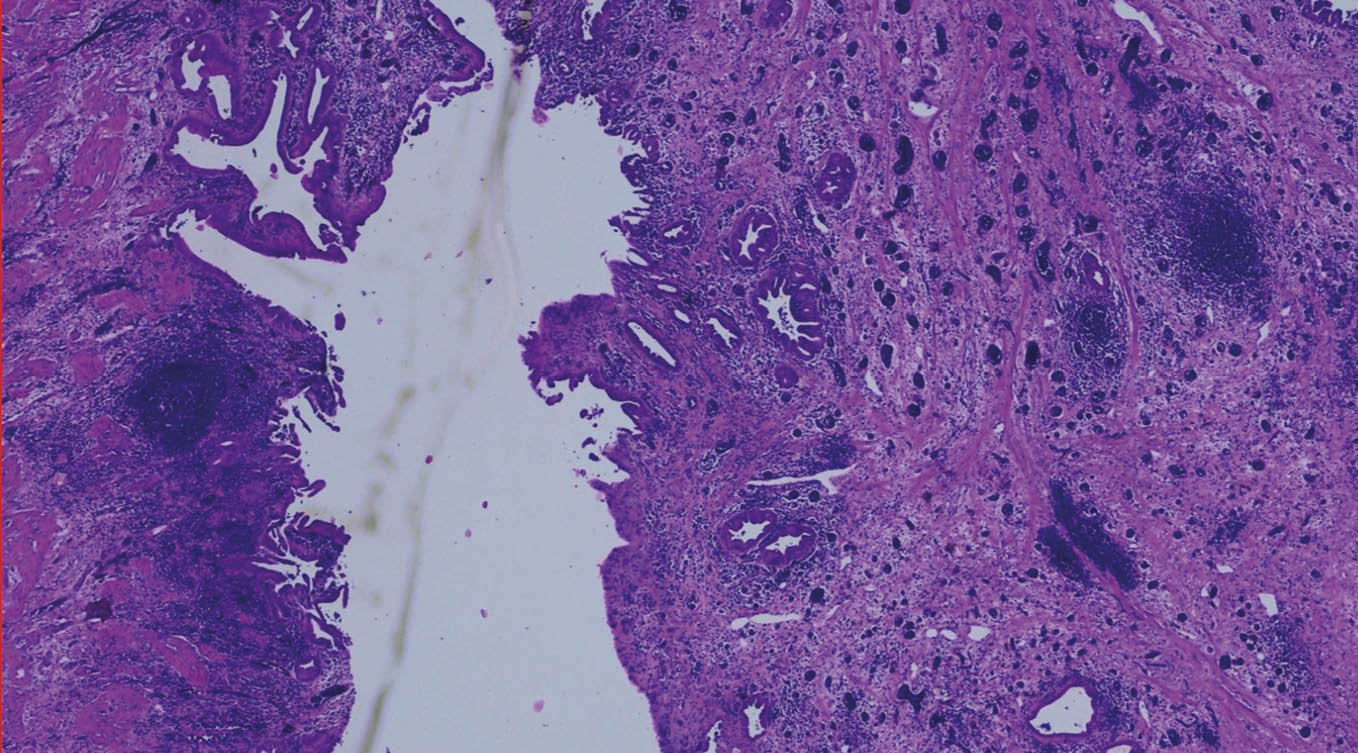

Laparoskopische Cholezystektomie für symptomatische Cholezystolithiasis (CCL) bei „Kasabach-Merritt-Syndrom“ (KMS)